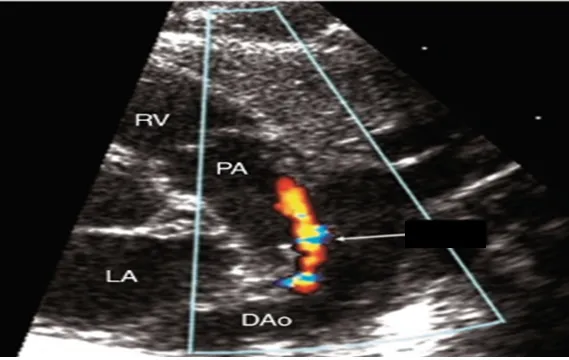

임신 기간 34주, 체중 2,150g으로 태어난 여아가 출생 후 바로 호흡곤란과 청색증을 보여 신생아호흡곤란증후군으로 진단받고 기계호흡기와 계면활성제 치료를 받은 후 상태가 호전되었다. 그러나 생후 7일째 다시 호흡곤란이 나타나며 산소포화도가 떨어지고, 가슴에서 심잡음이 들렸다. 심초음파 검사 결과가 나왔다. 이 아기에게 필요한 치료는 무엇인가?

• 현재 심초음파 상 뚜렷한 동맥관 개존이 관찰된다. 동맥관 개존증은 미숙아에서 높은 빈도로 나타나며, 특히 신생아 호흡곤란 증후군을 겪은 뒤 잘 합병된다.